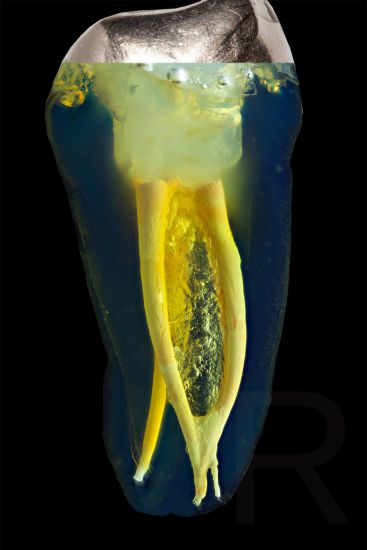

Das Verfahren, Zähne in durchsichtige Präparate zu überführen ist schon über 100 Jahre alt. Aber erst durch die Weiterentwicklung der alten Technik und die Kombination mit moderner Fotografie sowie der Entwicklung eines geeigneten Gefäßes zur Fotografie ist es meinem Vater Dr. Holm Reuver gelungen, einzigartige Bilder vom Inneren der Zähne aufzunehmen.

Die Bilder sind in verschiedenen Größen wählbar und auch als POPART-Variante erhältlich. Sie sind hervorragend geeignet für die Beratung von Patienten vor endodontischen Behandlungen, aber auch ein beliebter Eyecatcher im Wartezimmer. Außerdem haben die Bilder einen bedeutenden Stellenwert für die Erforschung der Pulpatopografie und für die Lehre im Bereich der Endodontie.

CLEARINGSERVICE bietet Ihnen die Möglichkeit, wurzelgefüllte Zähne mit der Technik des Transparentmachens untersuchen zu lassen. Das geht sehr einfach: Sie schicken uns den zu untersuchenden Zahn, dieser wird dann in ein transparentes Präparat überführt und mit hochwertiger Makrofotografie ausgewertet. Anschließend bekommen Sie die angefertigten Präparate zusammen mit der Fotodokumentation zugeschickt.